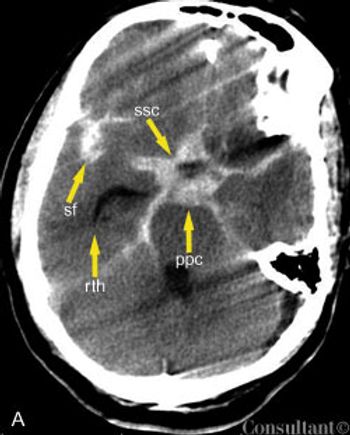

A 57-year-old man complained of a severe headache of sudden onset while he was lifting heavy boxes. Within minutes, he collapsed and became unconscious. On arrival at the emergency department, the patient was deeply comatose. His pupils were 7 mm, fixed, and unreactive to light; brainstem reflexes were absent, and he was unresponsive to noxious stimulation. His blood pressure was 210/120 mm Hg; he had no known history of hypertension.